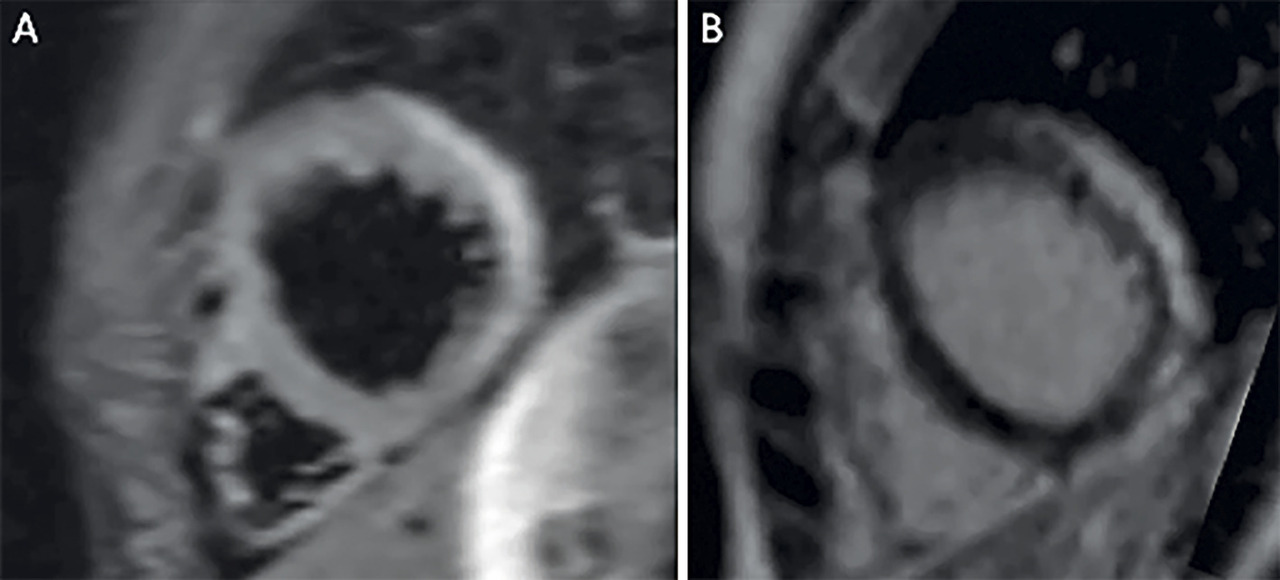

Ces critères permettent d’adresser le patient aux centres de référence pour l’imagerie spécifique et la biopsie endomyocardique. Cette dernière reste le gold standard pour confirmer le diagnostic (critères de « Dallas » : infiltration inflammatoire myocardique – leucocytes ≥ 14/mm2 incluant jusqu’à 4 monocytes/mm2 avec lymphocytes T CD3 positifs ≥ 7 cellules/mm2 – avec dégénérescence myocytaire et nécrose des cellules, d’origine non ischémique)2mais l’IRM est actuellement l’examen de référence pour caractériser avec précision le tissu myocardique inflammatoire (v. figure).

• Caractérisation tissulaire en IRM

Œdème et/ou rehaussement tardif.